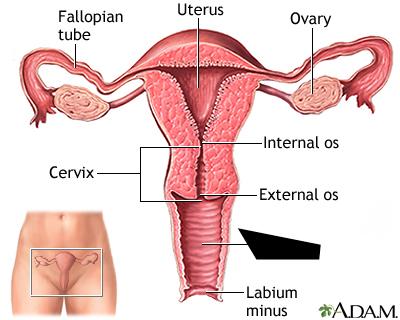

Cervix

Clitoris

Endometrium

Labia majora/minora

Myometrium

Overian ligament

Ovary

Perimetrium

Prepuce (=clitoral hood)

Uterine (=fallopian) tube

Uterus

Vagina

Vaginal orifice

Vestibule (of vulva)